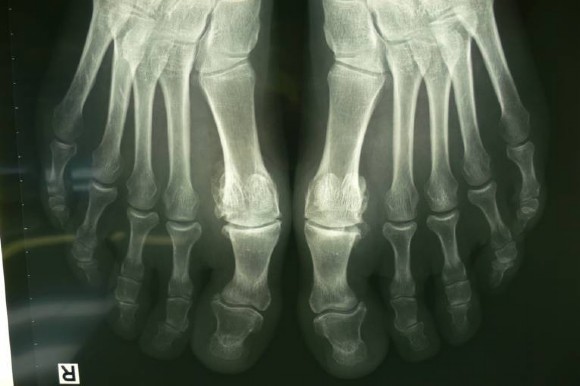

Eine Patientin mit Hallux rigidus, sie hat Schmerzen in beiden Großzehengrundgelenken. Ein normales Abrollen ist nicht mehr möglich. Fehlstellung und Schmerzen auch in beiden 2. Zehen, an den Endgelenken massive Fehlstellung nach außen, die durch den Hallux mit verursacht ist.

Im Röntgen: Schwerer Hallux rigidus Stadium 3 beidseits und Fehlstellung der Großzehen nach außen, sowie beiden 2. Zehen an den Endgliedern.

Sehr schlechte Beweglichkeit im deformierten und aufgetriebenen Großzehengrundgelenk. Schmerzen beim normalen Gehen, Abrollen über die Großzehe ist nicht mehr möglich, sondern es sind Ausweichbewegungen über den Fußaußenrand notwendig, die zu Knie-, Hüft- und Rückenschmerzen führen können.